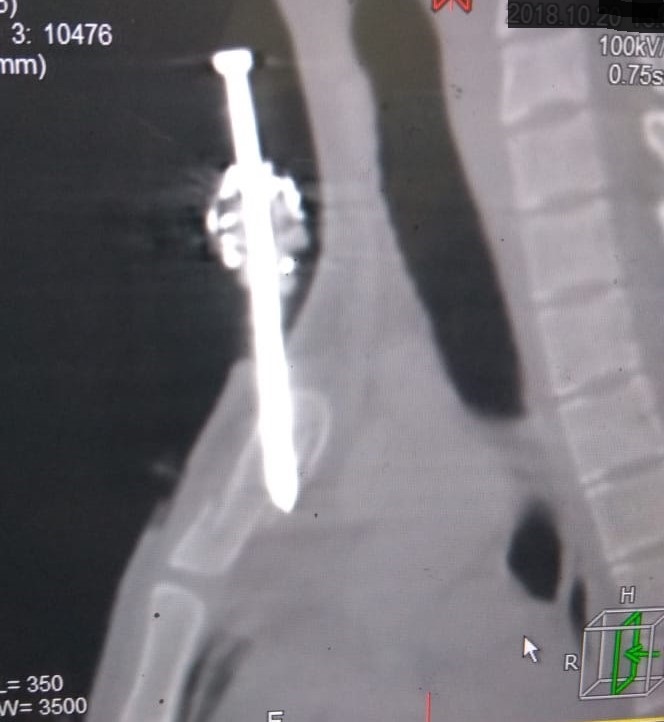

Figure 2. Computed tomography of the chest, sagittal view showing the fired nail traversing the manubrium obliquely with the long axis of the nail parallel to the long axis of the neck. Just the nail tip in the superior mediastinum.

Computed tomography (CT) of the chest with IV contrast revealed a nail penetrating the manubrium (Figure 2). The penetration was in a vertical orientation with slight oblique direction, with the entry point located at the superior end of the anterior plate (about 0.5 cm right of the sternal notch) and penetrating the mid part of the posterior plate as seen in the sagittal view of the CT scan, with just a few millimeters of the nail penetrating into the superior mediastinum. In the sagittal view of the CT scan, one can see fissure fracture of the posterior and anterior plates of the manubrium sterni at separate levels (Figure 2), so the stability of the sternum was not affected.